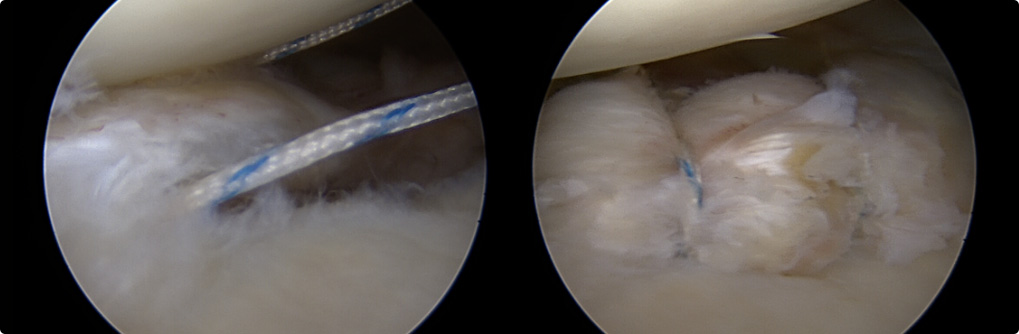

관절와순 봉합술

관절 내시경을 통해 파열된 관절와순을 정상적인 모양으로 봉합하여 제 기능으로 회복시켜 줍니다.

재발성 탈구(2회 이상)인 경우

첫 탈구이나 관절와순이 전위되어 있어

재탈구 가능성이 높은 경우

운동선수나 스포츠 매니아는 적극적으로 고려해야 함